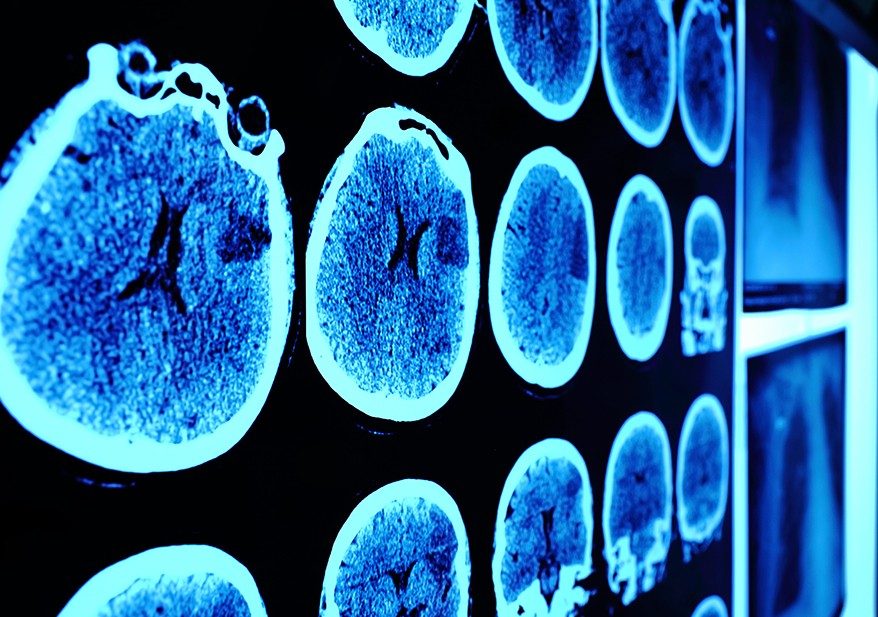

MD Anderson study shows FGL2 protein may be an effective target for glioblastoma

Researchers at The University of Texas MD Anderson Cancer Center have discovered an immune regulator that appears to dictate glioblastoma (GBM) progression by shutting down immune surveillance, indicating a potential new area of therapeutic investigation.

Findings from the preclinical study led by Shulin Li, Ph.D., professor of Pediatrics, and Amy Heimberger, M.D., professor of Neurosurgery, were published in the Jan. 25 online...